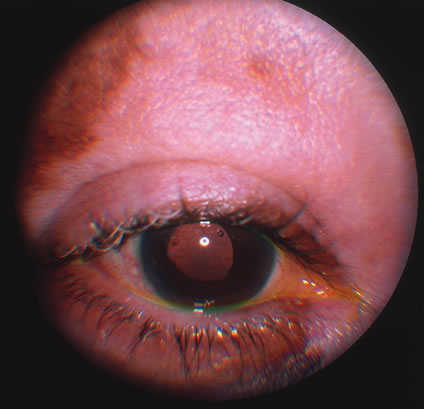

Rubella infections that occur early in gestation are associated with the greatest risk of fetal damage, however, infection in the third trimester may still cause damage. Maternal infection in the first 2 months of pregnancy results in a 40% to 60% chance of multiple congenital anomalies or fetal death. Congenital heart disease, cataracts, and deafness are the classic triad of the congenital rubella syndrome; however, there are many other commonly recognized complications of prenatal rubella infection (Fig. 13). Encephalitis, microcephaly, mental retardation, intrauterine growth retardation, thrombocytopenic purpura, hepatosplenomegaly, obstructive jaundice, interstitial pneumonitis, myocarditis, and radiolucent bone lesions are all possible sequelae of congenital rubella infection.54 The classic salt-and-pepper retinopathy occurs less commonly (Fig. 14), but may be noted to show progression. Other ocular findings include congenital cataracts, microphthalmia and glaucoma. Ocular disease and hearing loss frequently occur together, and glaucoma is frequently associated with microphthalmos.56

Fig. 13. A patient with the congenital rubella syndrome. Note the hearing aids, left esotropia, left microphthalmos and cataract.